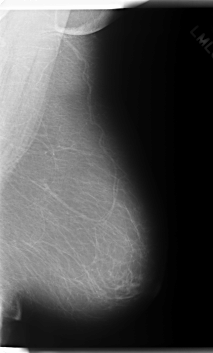

C_0236_1.LEFT_MLO

LEFT_MLO LINES 6000 PIXELS_PER_LINE 3616 BITS_PER_PIXEL 12 RESOLUTION 50 NON_OVERLAY